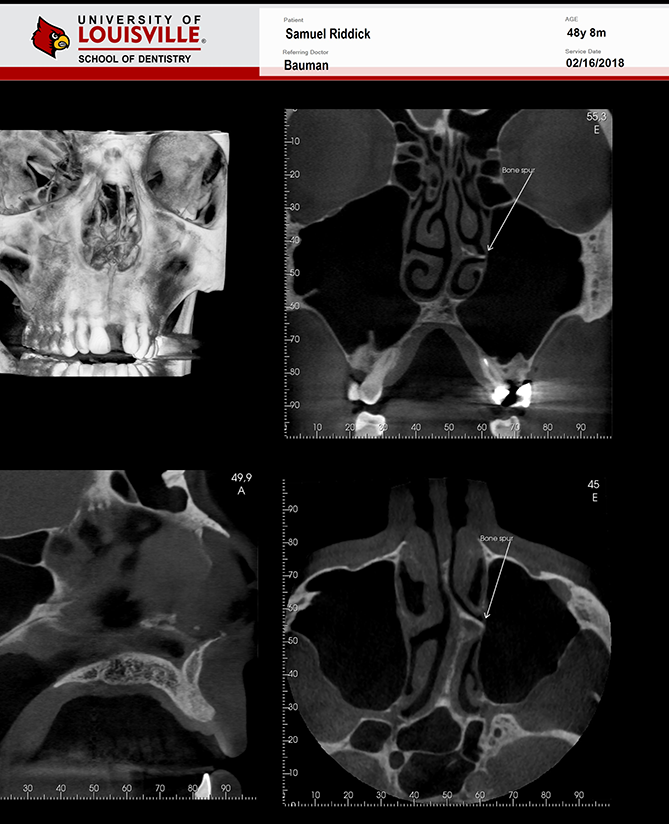

Este é um paciente masculino de 48 anos de idade e foi encaminhado para a clínica de Radiologia oral e maxilo-facial na Universidade de Louisville para uma aquisição de tomografia de feixe cônico da face para planejamento de implante.

Uma tomografia da maxila foi adquirida para avaliação do dente 21 e dos dois seios maxilares. Durante a interpretação do exame foi notado uma área ovalada, multilocular grande, bem definida, corticalizada na região retroclival prepontine. Este achado é fortemente consistente com Ecchordosis Physaliphora. Ecchordosis physaliphora é uma lesão hamartomatosa benigna congênita e pode ser encontrada em qualquer lugar da base do crânio ao osso sacrum. Também notei um forame jugular assimétrico no lado direito. Note que as margens são corticalizadas e não há sinais ou erosão / padrão mordida de traça. O aumento do forame jugular tornando-o assimétrico é fortemente consistente com Bulbo Jugular Alto. Esta variante anatômica ocorre mais comumente do lado direito. Há uma grande e fina espora óssea decorrente da parede lateral esquerda do septo nasal estendendo todo o caminho até a parede lateral esquerda da cavidade nasal.